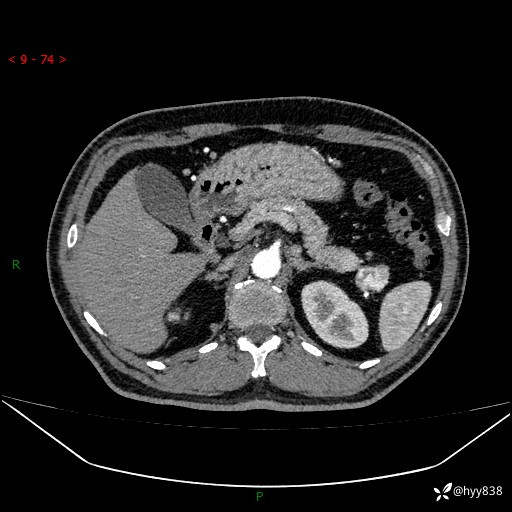

静脉期